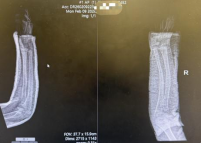

复位成功后,孩子原本扭曲变形的前臂也恢复了正常轮廓。团队为患儿采用超腕超肘石膏托进行外固定。这种特殊固定方式既能有效维持复位后的位置、防止再移位,又能通过精准塑形贴合前臂生理弧度,为骨折愈合提供稳定而舒适的环境。复位后即刻复查的X线片正位片显示,桡骨与尺骨骨折端对位良好,侧方移位完全纠正;侧位片显示掌背侧成角畸形已有效矫正,力线接近正常。“对于4岁的儿童而言,这样的复位效果已非常理想。”董博主任向家属耐心解释道,“儿童骨骼具有远超成人的塑形能力,即使存在轻微对位不良或小角度成角,在后续生长发育过程中也能自行重塑。因此,临床并不要求绝对解剖复位,而是在保障功能恢复的前提下,尽可能减少创伤。”